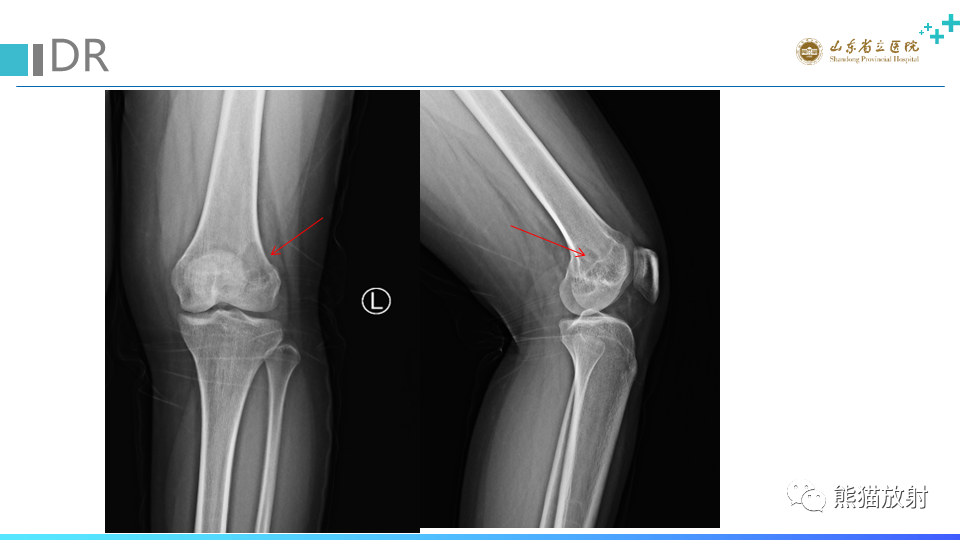

【病例】股骨远端动脉瘤样骨囊肿ABC VS 软骨母细胞瘤-5

【病例】股骨远端动脉瘤样骨囊肿ABC VS 软骨母细胞瘤-6